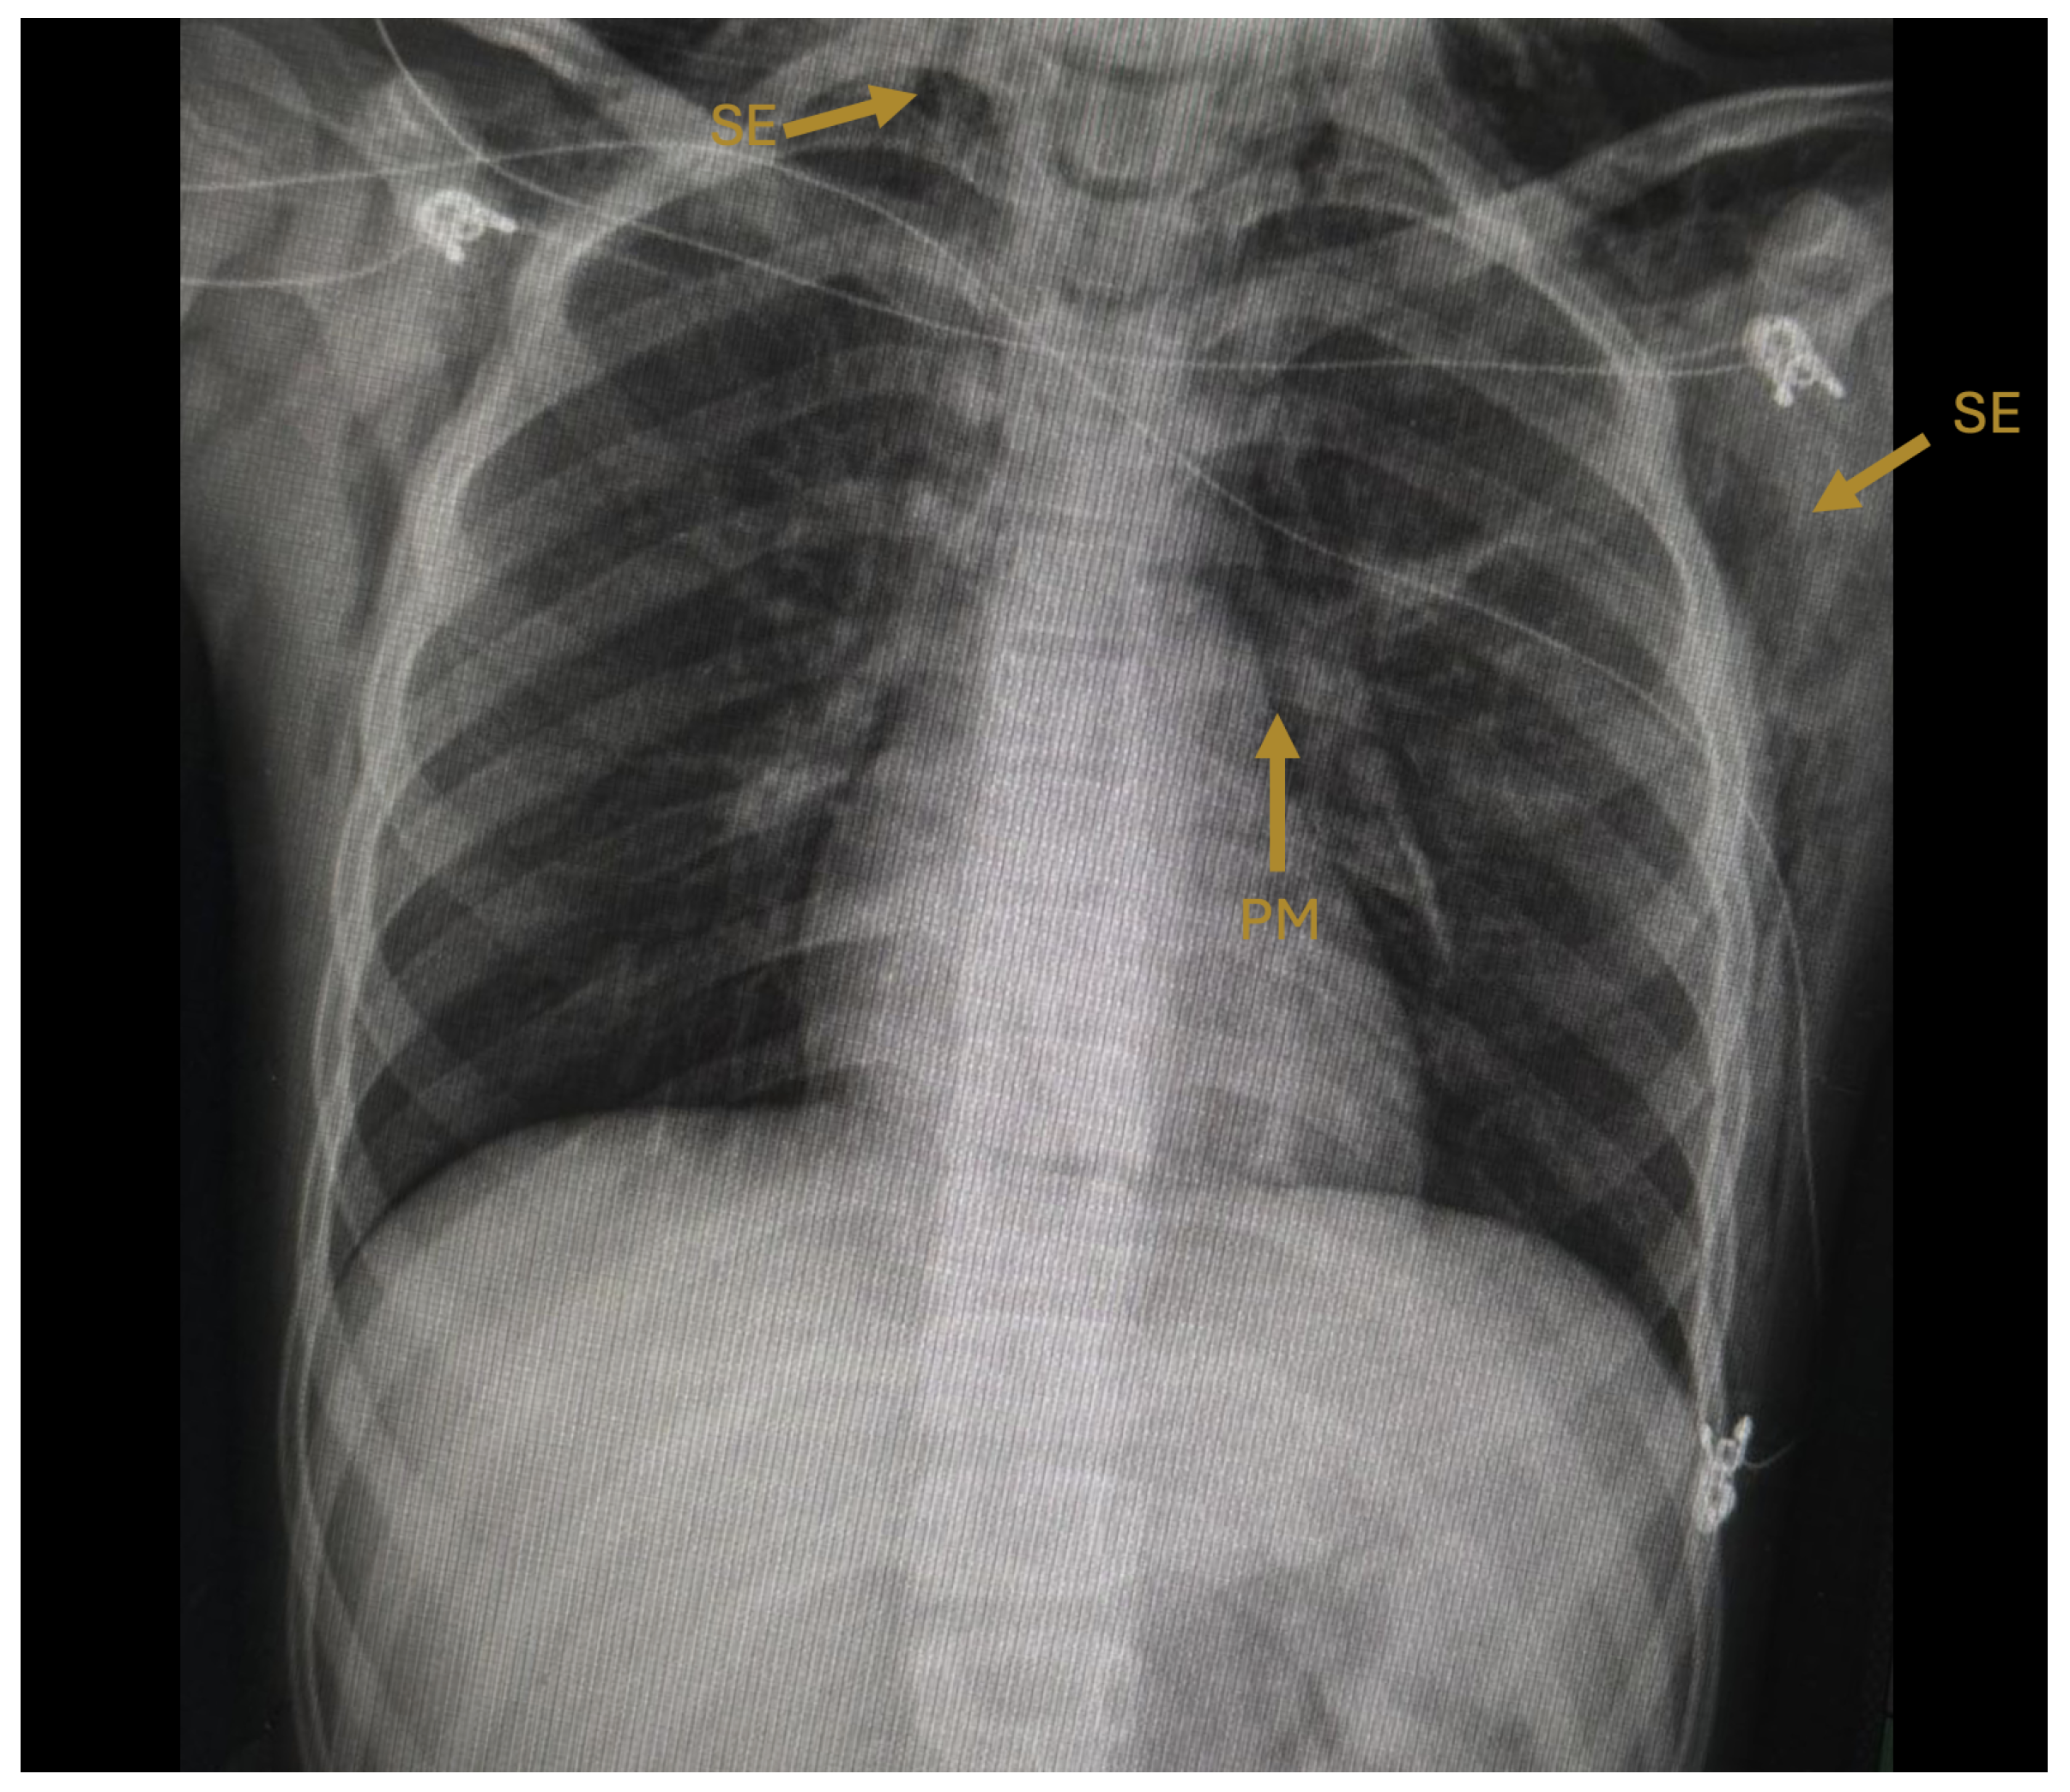

The initial chest radiograph demonstrated pneumomediastinum and extensive subcutaneous emphysema extending from the skull base to the mid-thorax, with a central trachea and normal pulmonary parenchyma (Figure 1). On hospital day 2, computed tomography (CT) of the chest confirmed pneumomediastinum with air dissecting along the esophagus, trachea, and pericardium, as well as a left-sided pneumothorax, pneumoperitoneum, and subcutaneous emphysema extending through the cervical, shoulder, and pectoral musculature (Figure 4).

Figure 1. Initial posteroanterior chest radiograph (hospital day 1). Arrows indicate pneumomediastinum (PM), visible as a radiolucent halo outlining the cardiac silhouette, and subcutaneous emphysema (SE) dissecting through the cervical and pectoral soft tissues bilaterally. The trachea is midline and pulmonary parenchyma appears without consolidation.

Of note, the pneumomediastinum was identified on the initial chest radiograph at admission, before any clinical deterioration, consistent with the observation by Bloch and Vardy that this complication may be radiographically apparent before it is clinically suspected [7]. This finding underscores the importance of careful radiographic interpretation in patients presenting with measles and respiratory symptoms.